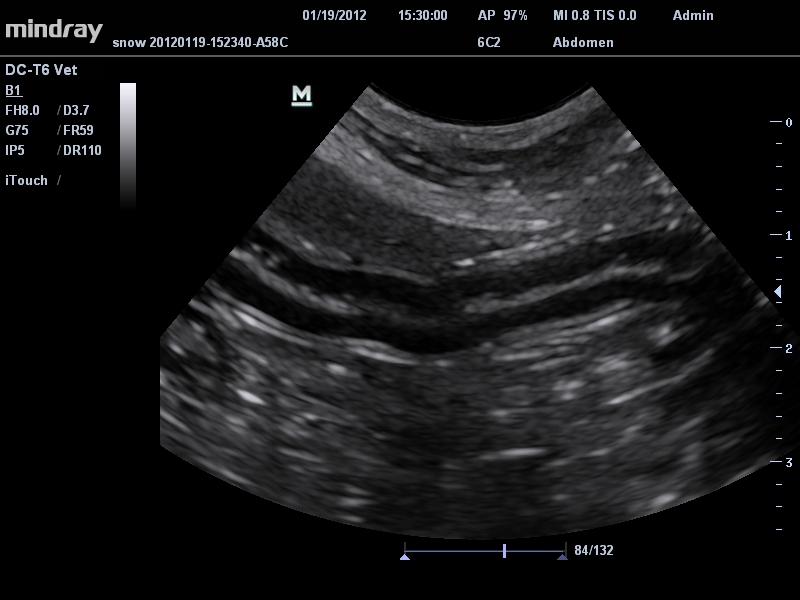

Mindray DC-T6

Ультразвуковая система Mindray DC-T6 – это инновационный аппарат для проведения высокого уровня диагностики с качественной визуализацией и широким спектром применения. Платформа рекомендована для использования в коммерчески многопрофильных медицинских учреждениях и государственных лечебных клиниках.

Ветеринария:

Да

• Микроконвексный датчик Mindray 6C2